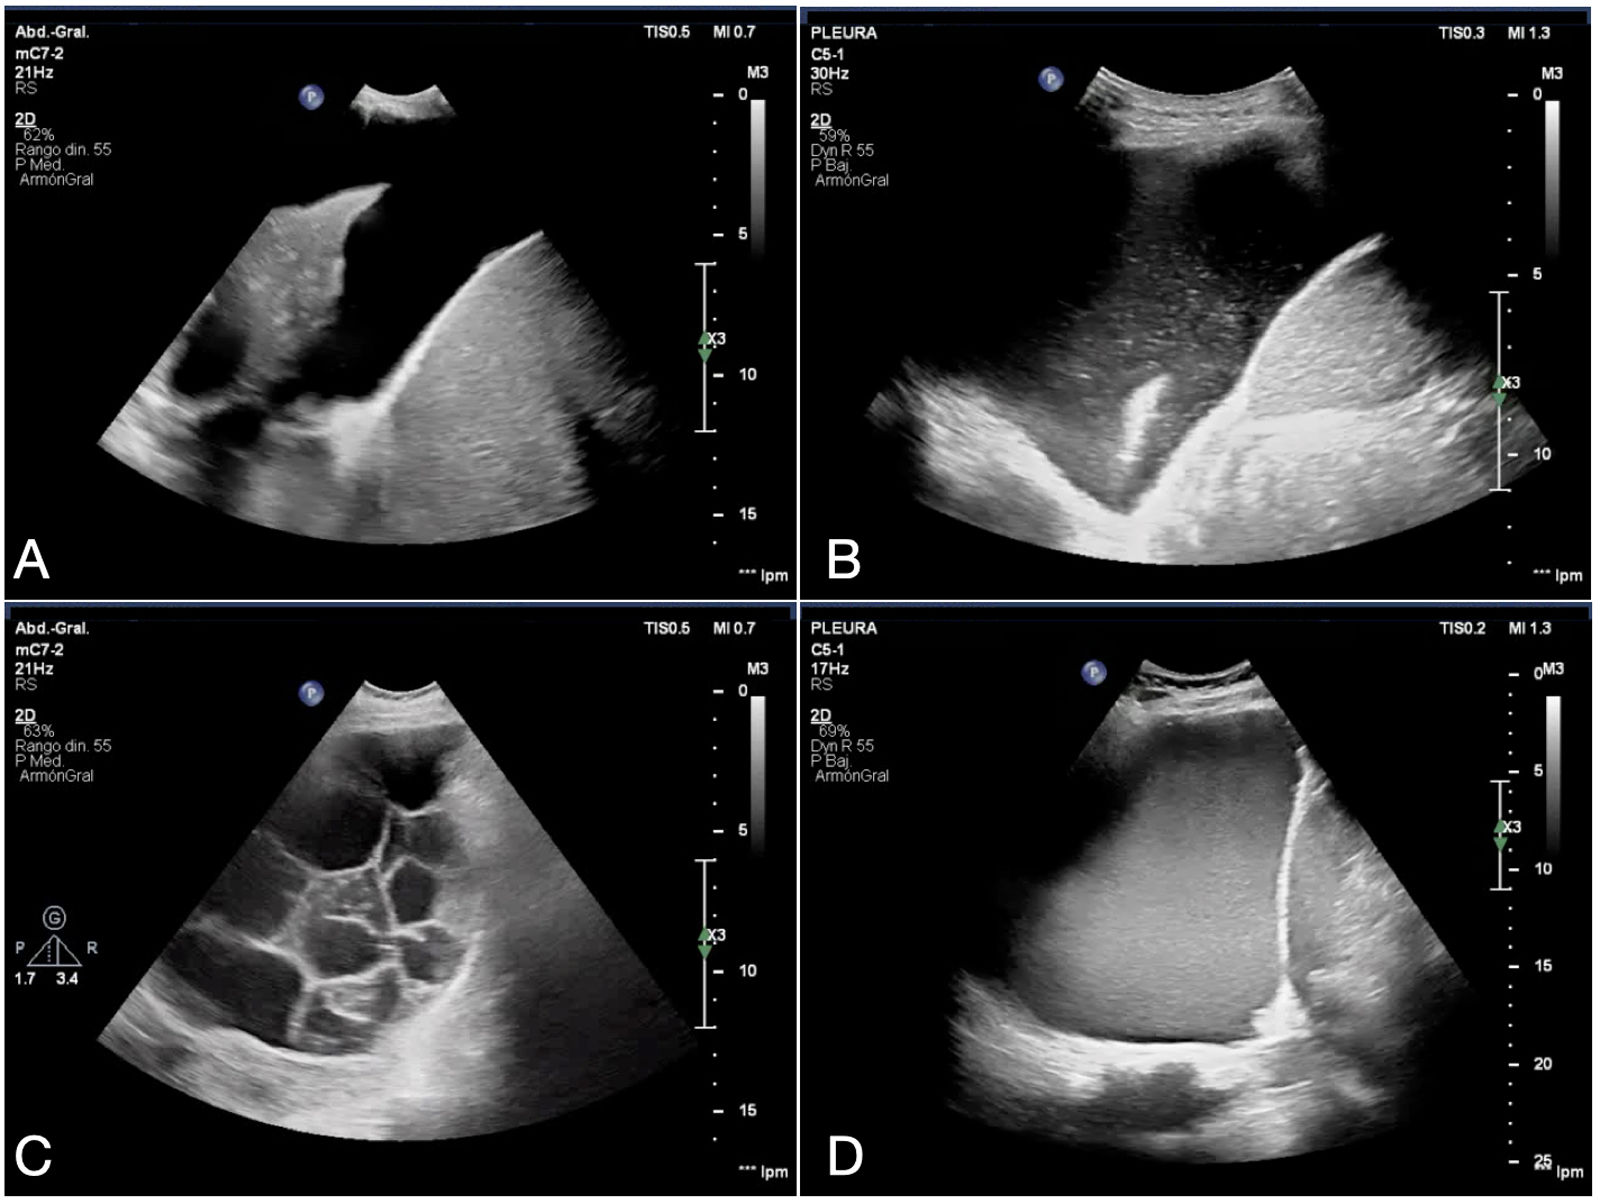

Point-of-care ultrasound (POCUS) is a rapid bedside imaging modality available to clinicians for the diagnosis of pleuropulmonary infections. Compared with chest radiography, POCUS is more sensitive in identifying pneumonia and its complications (parapneumonic pleural effusions, necrosis, and abscesses). The most common sonographic features of pneumonia are consolidation (with irregular margins and dynamic air bronchograms), B-lines, and pleural effusion. POCUS also has prognostic applications, for example, to determine the severity of COVID-19 pneumonia or to predict residual pleural thickening in a tuberculous effusion. Finally, the presence of a complex septated ultrasound pattern in the context of pleural infection is indicative of the need for drainage, which is performed using a thoracostomy tube and instillation of intrapleural enzyme therapy.

El ultrasonido en el punto de atención (point-of-care ultrasound [POCUS]) es una modalidad de imagen rápida y disponible a la cabecera del paciente para el diagnóstico de las infecciones pleuropulmonares. En comparación con la radiografía de tórax, el POCUS es más sensible para identificar la neumonía y sus complicaciones (derrame pleural paraneumónico, necrosis y abscesos). Los signos sonográficos más comunes de la neumonía son la consolidación (con márgenes irregulares y broncograma aéreo dinámico), las líneas B y el derrame pleural. El POCUS también tiene implicaciones pronósticas, por ejemplo, para determinar la gravedad de una neumonía por COVID-19 o predecir el engrosamiento pleural residual en un derrame tuberculoso. Por último, la presencia de un patrón ecográfico complejo septado en el contexto de una infección pleural es indicativo de la necesidad de un drenaje, que se realiza mediante un tubo de toracostomía y la instilación de terapia enzimática intrapleural.